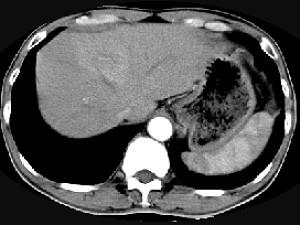

问题 男,61岁,寒战高热,右上腹痛,白细胞计数升高,CT检查如图,最可能的诊断是 ( )

选项 A、炎性肉芽肿 B、肝转移瘤 C、肝血管瘤 D、肝脓肿 E、原发性肝癌

答案 D